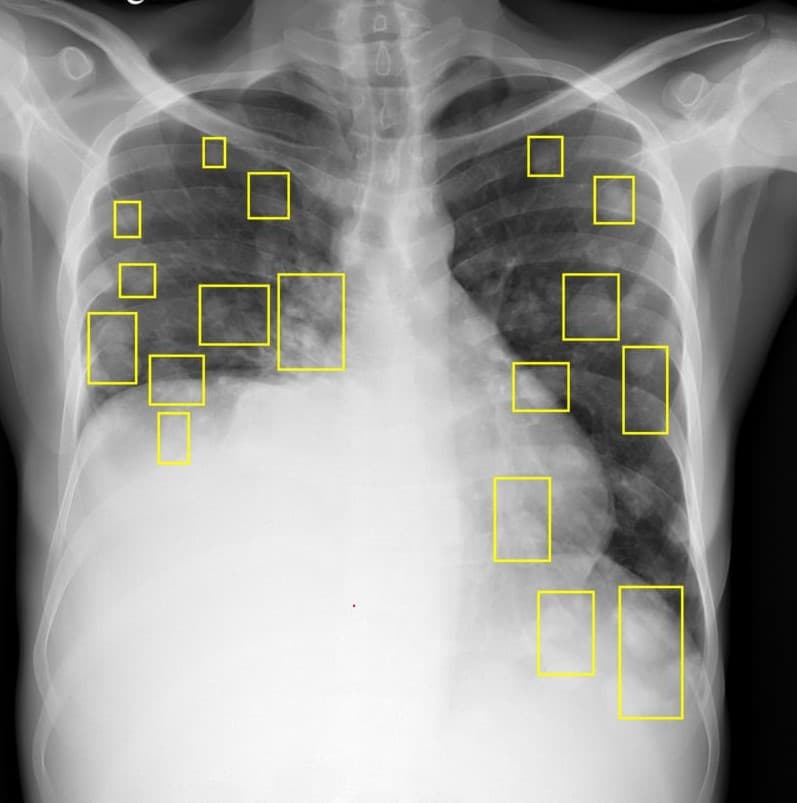

Chest X-Ray Annotation

Specialized chest X-ray annotation with radiologist oversight. Identify pneumonia, cardiomegaly, pleural effusions, and other thoracic conditions.